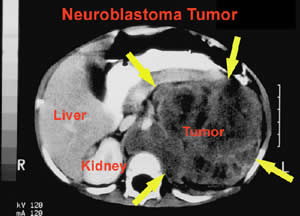

É uma doença maligna que ataca principalmente as crianças. Tumor formado por neuroblastos, (células em estado de divisão celular) que se localizam na glândula supra-renal. O neuroblastoma pode, em alguns casos, apresentar regressão espontânea, mas como é um tipo de câncer muito agressivo, pode aparecer em crianças com idade de até seis meses, sendo assim caberá ao Pediatra detectar a doença e encaminhar.

É uma doença cujas células malignas vão ser encontradas em algum lugar do sistema nervoso periférico, no entanto é mais comum que se estabeleça nas glândulas denominadas adrenais, que se localizam nos rins e são compostas por dois tecidos de origem embrionárias diferentes, um produzindo os esteróides e o outro, os neurotransmissores, são Maravilhas da Engenharia do corpo humano. Existem catalogadas 125 tipos de doenças das glândulas supra-renais, mas a ¨neuroplasia¨ das glândulas supra-renais, é a única que tem o índice 100 de valoração. Essas glândulas são responsáveis pela produção de hormônios e pela defesa dos perigos emocionais, do equilíbrio do sal, entre outros.

Não existe nenhuma doença boa, mas o neuroblastoma é terrível, a começar pelo seu aparecimento que geralmente se estabelece antes do nascimento do bebe, mas só é detectado quando o tumor começa a crescer e tomar forma e só a partir daí gera sintomas; e sua propagação, se não tratado a tempo, vai se dar para os glândios linfáticos, para a medula óssea, para o fígado ou para a pele, e neste estágio Só Deus Salva. Alguns sintomas podem ser visíveis e acusam o aparecimento da doença, como por exemplo, a ocorrência de massa ou de protuberância no abdômen, na região do pescoço, no tórax, podendo ocorrer também manchas escuras em torno dos olhos, ou ainda, os olhos ficam saltados. Apesar de não existir comprovação cientifica sobre as causas do neuroblastoma, existem estudos publicados associando a exposição do feto ao Alcoolismo, a certos medicamentos, a tinta para cabelos, hormônios, etc., mas não há nada cientificamente comprovado.

Apesar dos estudos científicos sobre a origem da doença, os fatores de risco ainda continuam desconhecidos, já os recursos para um diagnóstico da doença ainda na infância são vários, como por exemplo, a biópsia, que promove a remoção de células do tumor para exames de laboratório, mas ai a doença já existe. Outro método que é muito utilizado e que apresenta bons resultados, é a tomografia computadorizada que fotografa todo o corpo do paciente, auxiliando Como Cuidar Melhor da Nossa Saúde e diagnosticar uma recuperação do paciente. Só para exemplificar, dois atores podem implicar em uma possibilidade mais concreta de recuperação do paciente, a idade e quando diagnosticado, o estado do câncer. Fora isso, é pedir uma Ajudinha de Deus para que à luz da ciência, seja descoberta a sua cura.